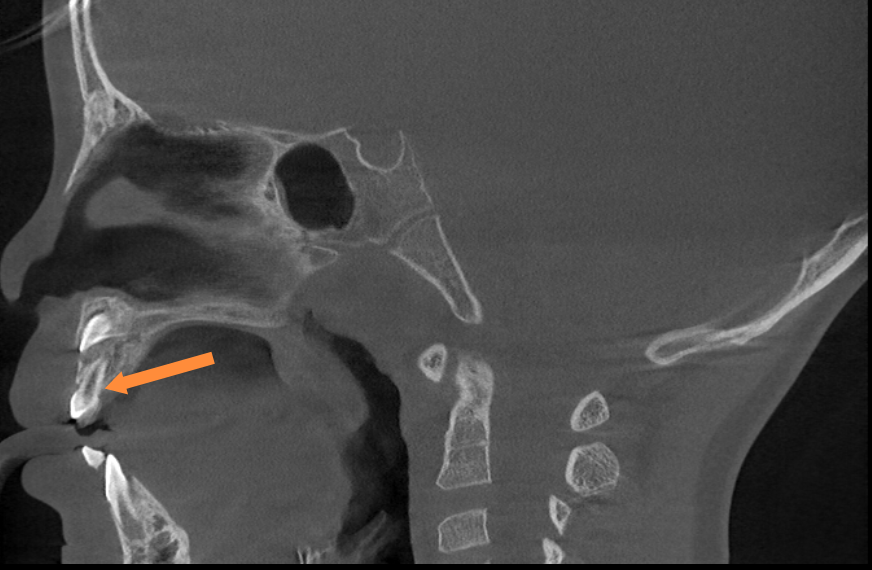

近日,我院口腔科与麻醉科的共同协作下顺利完成首例儿童镇静下口腔治疗。5岁女童因多生牙曾多次到我院口腔科寻求治疗仍无法取得患儿配合。随后在口腔科程敬雨主任与麻醉科唐国值主任的沟通下,最终确定治疗方案:在门诊行镇静监护下进行口腔治疗,家长表示理解并完全赞同实施该方案。

术前口腔CBCT检查

“镇静下拔牙”通常是指在镇静技术的辅助下进行拔牙,并持续监测患者生命体征,与全麻不同的是患者是处于放松的、嗜睡的状态。其优势是:极大程度上消除患者焦虑和恐惧情绪,提升舒适度,减少生理应激反应,为口腔医生提供更理想的操作条件和便于处理复杂病例。该技术适合极度牙科恐惧症患者,儿童或有特殊需求无法配合治疗的患者。